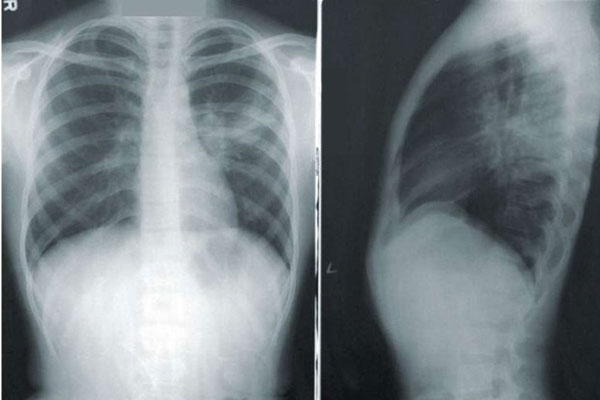

Khi cơn đau lưng trở nên trầm trọng, cảm giác “cắn trong xương”, chị N. đến bệnh viện kiểm tra. Qua phim chụp, bác sĩ thấy có tổn thương ở cột sống và nghi ngờ u ở xương. Các kết quả cận lâm sàng chuyên sâu phát hiện hình ảnh khối mờ trung tâm thùy trên phổi trái kích thước 22x32mm, bờ tua gai, xâm lấn trung thất, phế quản gốc. Bác sĩ chẩn đoán ung thư phổi di căn sang cột sống, có hiện tượng hủy xương ở vùng bả vai, cột sống, cánh tay.